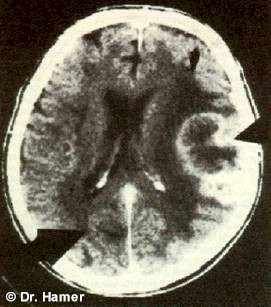

Во время этой первой фазы исцеления НН на томографическом снимке проявляется в виде темных концентрических колец (что указывает на наличие отека в этой части мозга).

Пример: на данном снимке виден НН в ПКЛ-фазе А, соответствующий опухоли легких, указывающий на разрешённый «конфликт страха смерти». Большинство подобных «конфликтов страха смерти», приводящих к раку легких, вызываются постановкой неблагоприятного диагноза с негативным прогнозом.